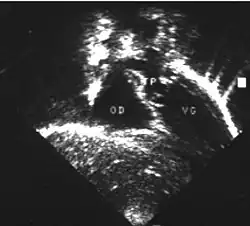

- Les coupes sous costales qui montrent bien le trajet parallèle des gros vaisseaux et leur inversion. Cet examen permettra d'éliminer en particulier un retour veineux pulmonaire anormal total bloqué qui aurait pu rendre compte de l’hypervascularisation pulmonaire sur la radiographie des poumons.